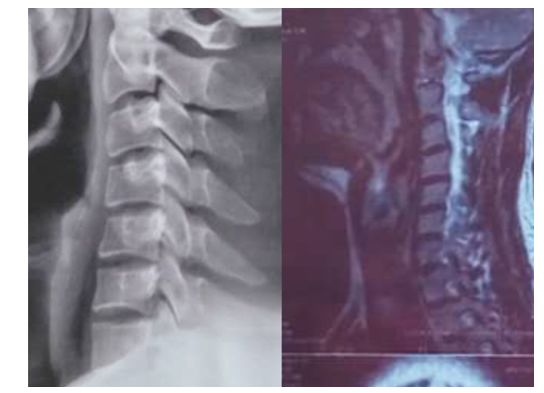

颈椎疾病普遍遇到一个问题,就是颈椎曲度变直,颈椎没有生理曲度,甚至反弓,影像报告上会清楚的注明:颈椎曲度浅直、变直或消失。但是很多医生是回避颈椎曲度变直这个问题,患者也自然忽视颈椎曲度消失这个情况,只知道颈椎间盘突出,严重了需要手术,却不了解颈椎曲度变直或消失与颈椎间盘突出的必要联系。

在临床上发现,很多核磁影像与X光影像对比,几乎所有颈椎间盘突出与颈椎变直是同时存在,就不得不考虑颈椎曲度变直与颈椎间盘退化的必要联系。